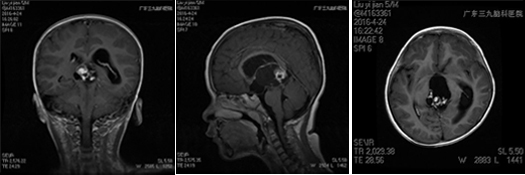

小刘在4月份的某一天上午上学时突然出现头疼,老刘赶紧带着孩子到当地医院就诊,给予对症处理,可是小刘还是感觉不舒服,结果没几天,小刘感觉头疼加重伴有呕吐,慢慢的变得意识模糊,老刘紧急送往当地儿童医院就诊,医生通过CT检查发现小刘为松果体及三脑室占位病变,梗阻性脑积水,给予脱水,降颅压,紧急行右侧侧脑室钻孔外引流术,术程顺利,术后给予相应治疗后小刘慢慢的神志清醒,头疼症状缓解,未再出现呕吐,老刘一家为了让小刘更好得康复,于是转院到广东三九脑科医院神经外七科进行治疗,神经外七科吾太华主任在详细了解小刘情况后,根据复查颅脑CT提示松果体及三脑室内占位病变,脑积水脑室外引流术后改变,遂以“松果体及三脑室占位,梗阻性脑积水”收治入院,入院后完善相关检查,进一步明确诊断,颅脑MR检查提示为松果体及三脑室内占位病变,考虑生殖性肿瘤,以成熟型畸胎瘤可能性大,幕上梗阻性脑积水脑室外引流术后改变,经积极术前准备,小刘在全麻下性松果体及三脑室内占位病变切除术,术程顺利,术后病理为松果体及三脑室不成熟畸胎瘤 WHO I级,复查颅脑MR提示原病变已切除,颅脑CT提示脑积水已缓解。

术前影像检查